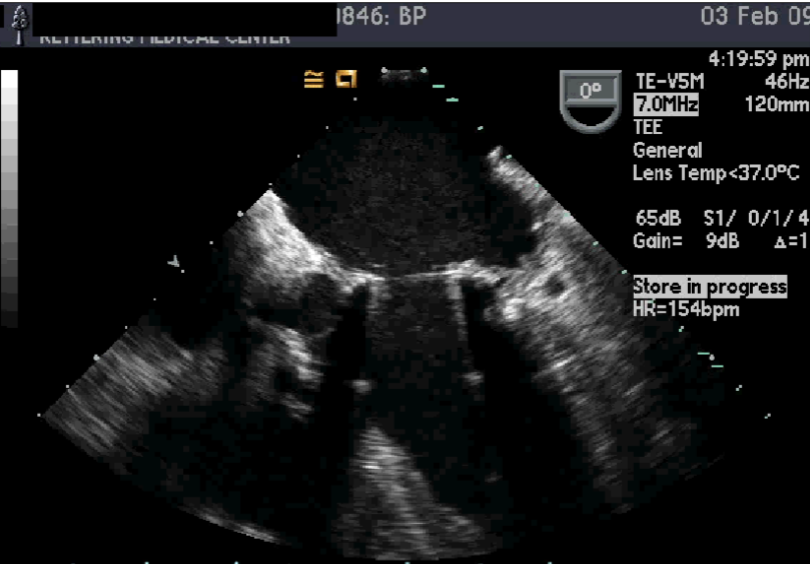

TEE Evaluation of Mechanical Valves:

method of choice

assess regurg

may be masked by prosthesis on TEE

assess anatomic detail:

LA appendange

thrombus / vege

ring abscess

pseudoaneurysm

intraoperative monitoring for:

perivalvular leak

regurg

dysfunction